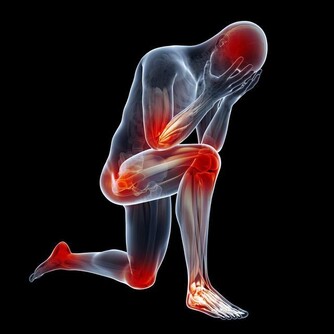

3、運動系統

運動系統腫瘤主要指骨癌,這類患者常因病情而作過截肢手術,術後的鍛煉以恢復運動功能為目的。鍛煉方式或以健側肢體彌補患側功能,如練習用單手料理生活;或以假肢或以拐杖代替患側肢體,如學會拄拐或用輪椅、學會正確應用假肢。此類運動量一般較大,患者常常由於術後疼痛或對殘疾的不接受而導致對鍛煉包括必需的鍛煉的不配和,此時需要耐心地給以精神上的安慰和生活上的照顧,練習時給予熱情幫助和指導,病人本人則要冷靜、有耐心,當經過鍛煉而學會活動和走路時,喜悅的心情能夠補償鍛煉時所付出的艱辛。

3、腫瘤患者的運動,要注意全身運動與局部運動相結合,這樣才能發揮其康復醫療的最大作用。一般可以全身運動為主,對於局部截肢或伴有腦血管病的患者,還應配合相應的局部運動和功能鍛煉。